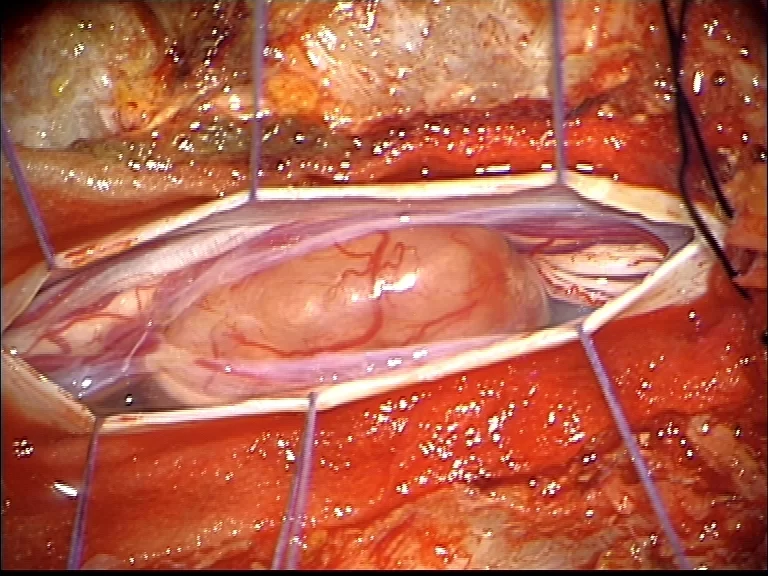

Οι ενδοσκληρίδιοι-εξωμυελικοί εντοπίζονται εντός της σκληράς μήνιγγας (δηλαδή του περιβλήματος του νωτιαίου μυελού) αλλά εκτός του νωτιαίου μυελού (Εικόνα 2). Η συχνότητα είναι περίπου 40% των όγκων σπονδυλικής στήλης. Οι πιο συχνοί τύποι είναι τα μηνιγγιώματα, τα επενδυμώματα του τελικού νηματίου, τα σβαννώματα και τα νευρινώματα. Πρόκειται στην πλειοψηφία τους για καλοήθεις όγκους.

Χειρουργική Αντιμετώπιση: Οι ενδείξεις και ο τρόπος χειρουργικής αντιμετώπισης εξαρτώνται απολύτως από τον τύπο του όγκου. Πρωτοπαθείς (μη-μεταστατικοί) όγκοι των σπονδύλων χρειάζονται ριζική αφαίρεση με σπονδυλεκτομές. Σε περίπτωση μεταστάσεων συνήθως αρκεί η αποσυμπίεση των νευρικών δομών και η συμπληρωματική ακτινοβολία. Το αν υπάρχει ένδειξη για χειρουργείο σε ασθενή με μεταστατική νόσο σπονδυλικής στήλης είναι κάτι που πρέπει να συζητηθεί και να συναποφασιστεί με τους ογκολόγους. Για ενδοσκληρίδους όγκους όπως πχ. μηνιγγιώματα ή νευρινώματα, καθώς επίσης για ενδομυελικούς όγκους (πχ. αστροκυττώματα ή επενδυμώματα) η θεραπεία είναι η ολική χειρουργική αφαίρεση. Συνήθως χρησιμοποιούνται ελάχιστα επεμβατικές μέθοδοι ενώ αποφεύγεται η καταστροφή των υγιών ιστών και δομών της σπονδυλικής στήλης (Εικόνα 3). Μερικοί όγκοι, όπως πχ. το λίπωμα νωτιαίου μυελού, αφαιρούνται ιδιαίτερα αποτελεσματικά με τη χρήση λέιζερ (laser) (Εικόνα 4).